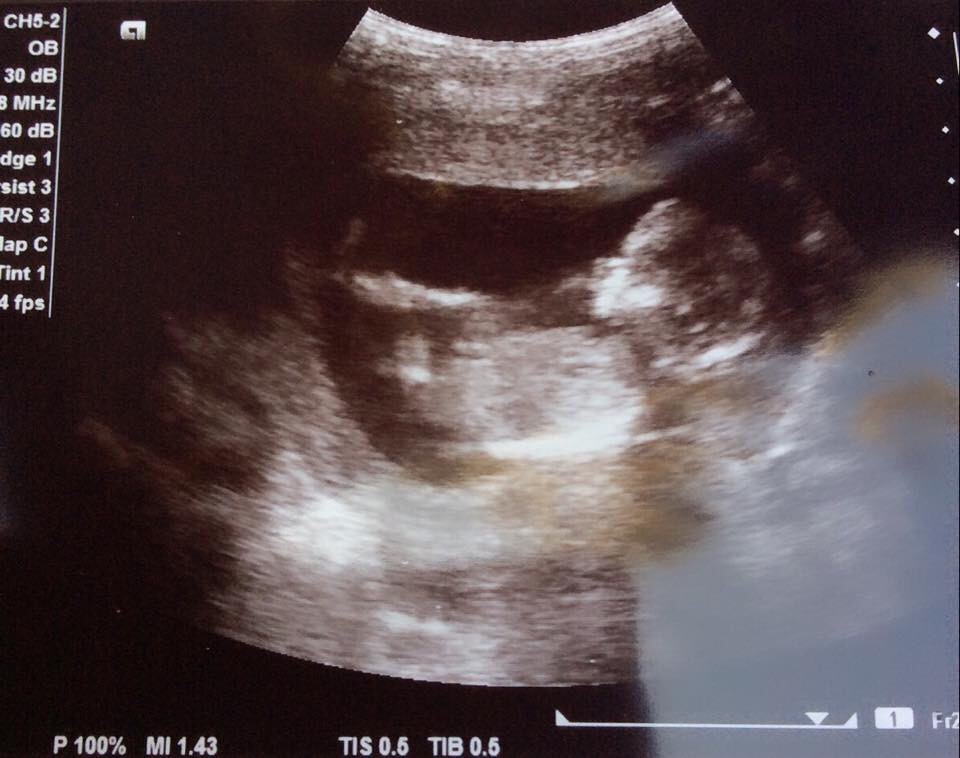

Anatomy Ultrasound Pics!